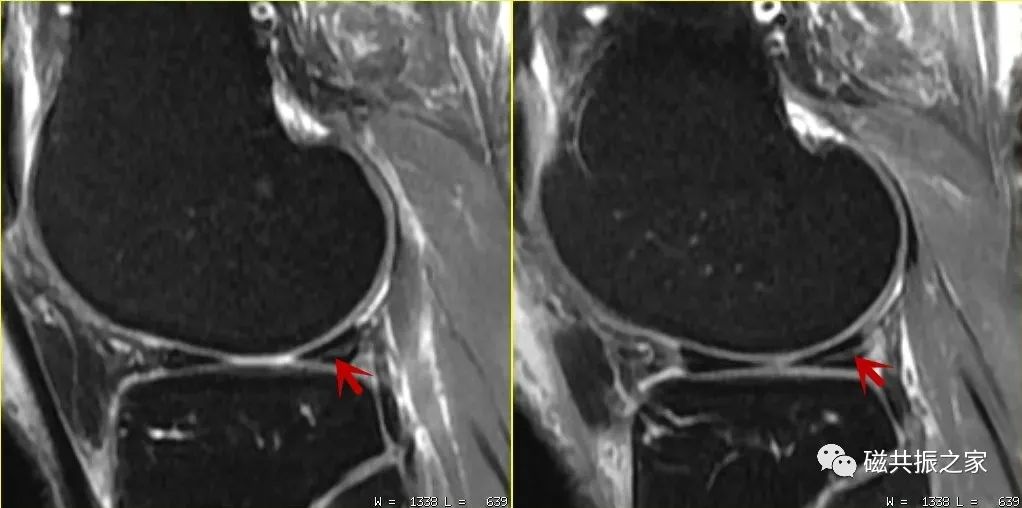

图△,这类伪影在四肢关节的扫描中并不少见。如不能正确地识别该类伪影,其很容易被误诊为水肿信号。在四肢关节的扫描中正确认识相应的伪影 ,是获得优异图像质量的关键。同时对相应伪影的正确认识,可以有效避免漏误诊的发生。

如魔角效应可出现在任何权重的MRI图像上,以短TE序列最为明显,如T1WI、PDWI图像上。常见于四肢关节的肌腱组织图像上,当在实际扫描中技师遇到该伪影时应知道如何去改善它,诊断医师遇到该伪影时应能正确识别它。